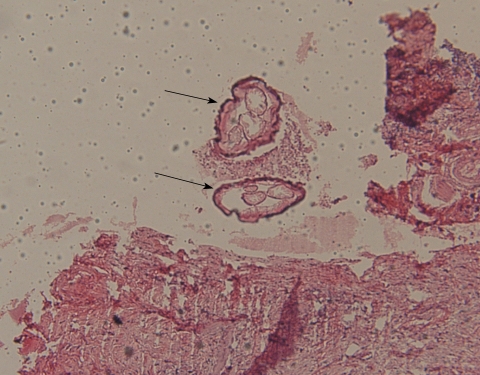

Histological examinations revealed multiple sections of a nematode with central eosinophilic and neutrophilic infiltration surrounded by granulomatous and fibrous tissues (Fig. 1). Morphologic evaluation showed a nematode with multilayer thick cuticles, indistinct intestinal cells, numerous external ridges, distinct dorsal and ventral fields of divided coelomyarian somatic musculature, 2 internal longitudinal ridges with broad lateral chords, heavy musculature, and didelphic uterine tubes with a small extra branch empty of microflariae. These findings suggested it to be a mature female worm of Dirofilaria repens (Fig. 2). Treatment with topical steroids was commenced.